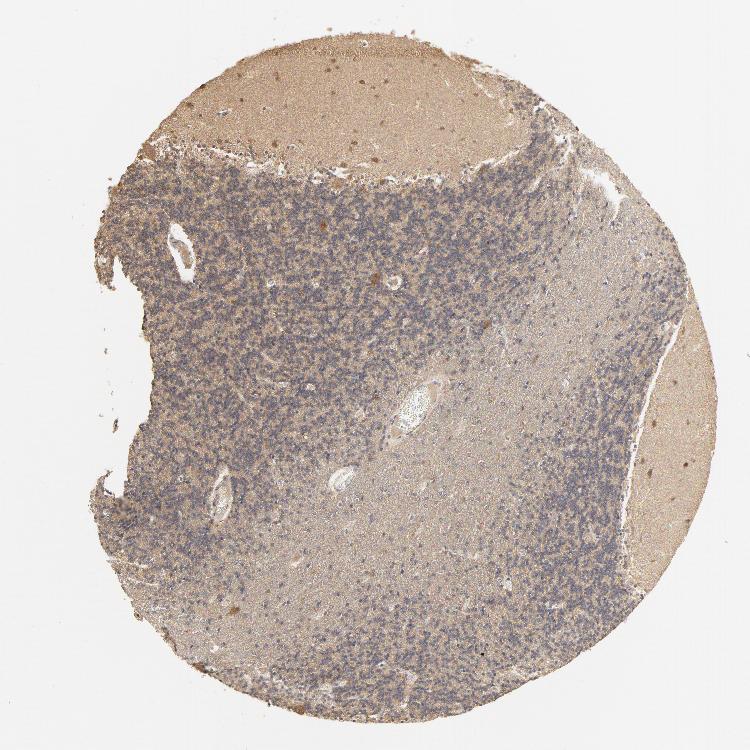

CEREBELLUM - Antibody stainingi

Antibody staining in the annotated cell types in the current human tissue is reported as not detected, low, medium, or high, based on conventional immunohistochemistry profiling in selected tissues. This score is based on the combination of the staining intensity and fraction of stained cells.

Each image is clickable and will lead to virtual microscopy that enables deeper exploration of all samples and also displays staining intensity scores, fraction scores and subcellular localization as well as patient and tissue information for each sample.

Antibody CAB004082

Purkinje cells High

Cells in granular layer Low

Cells in molecular layer Medium